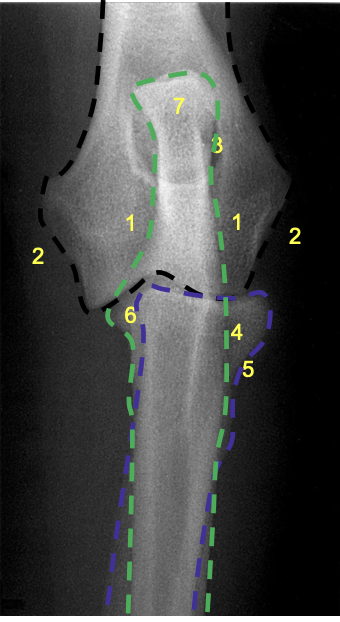

what is 1?

condyles of humerus

what is 2?

epicondyles of humerus

what is 8?

olecranon process of the ulna

what is 7?

olecranon of ulna

how does the olecranon process extend on a lateral view?

caudo-proximally

what is the relation of the medial condyle to the lateral condyle on a medio-lateral view of the elbow in a dog?

medial condyle is distal to the lateral condyle

where in the ulna is there a slight increase in opacity?

at the proximal extremity of the medullary cavity

where is the caudal ulnar cortex thicker?

in the proximal third of the diaphysis